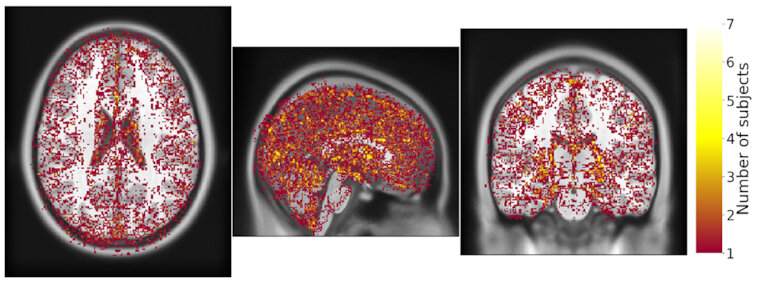

Same hardware, two Freesurfer builds (different glibc version)

Difference in estimated cortical tickness.¹

Same hardware, same FSL version, two glibc versions

Difference in estimated tissue segmentation.²

Same hardware, two Freesurfer builds (two glibc versions)

Difference in estimated parcellation.²

1. Glatard, et al., 2015 (Front. Neuroinform.) 2. Ali, et al., 2021 (Gigascience)